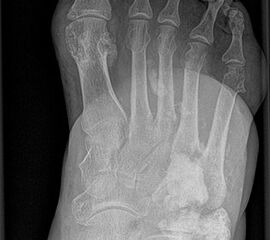

Konventionelle Röntgenaufnahmen bleiben in der bildgebenden Diagnostik von Knochen­tumoren das wichtigste diagnostische Werkzeug. Zahlreiche Informationen können hierdurch einfach, kostengünstig und im Vergleich zu einigen alternativen Untersuchungsmethoden strahlungsarm eingeholt werden. Die in der konventionellen Diagnostik eruierbaren und zur weiteren Abklärung erforderlichen Informationen beinhalten Befunde zu Topographie der Läsion (Lokalisation im Fußskelett und im individuellen Knochenbereich), Begrenzungen der Knochenläsion, Art der Osteodestruktion und Periostreaktion, radiologische Erscheinung der Tumormatrix (Zusammensetzung des Tumorgewebes, z.B. dystrophe Verkalkungen) sowie Verhalten und Ausmaß der Weichteilbeteiligung. Dabei sollte der abzubildende Knochen immer einschließlich der benachbarten Strukturen und angrenzenden Gelenke dargestellt werden. Die Röntgenaufnahmen sind stets in mind. zwei Ebenen anzufertigen. In Abhängig­keit der Beschwerden sind belastete Aufnahmen im Stehen anzustreben um zusätzliche Aussagen zur Statik zu erlangen. Die Schrägaufnahme des Fußes stellt eine sinnvolle Ergänzung zu den Standardeinstellungen (dorsoplantar/a.p. und streng lateral) dar um die Knochen des Fußskeletts möglichst überlagerungsfrei darstellen zu können. Ziel- und Spezialaufnahmen können bei Bedarf zusätzlich durchgeführt werden.

Das Enchondrom ist der häufigste Knochentumor im Bereich von Hand und Fuß und nach dem Osteochondrom der zweithäufigste gutartige Knochentumor überhaupt. Die geschlechtliche Verteilung ist ausgeglichen, Enchondrome finden sich meist bei Patienten zwischen 20-40 Jahren. Dieser chondrogene Tumor verhält sich meist asymptomatisch, kann aber durch eine Knochenexpansion und Schwellung sowie Spontanfrakturen (Abb. 17) auffallen. Radiologisch zeigen sich in der Regel gut abgrenzbare Osteolysen, Matrixverkalkungen sind typisch aber nicht obligat. Die MRT zeigt typischerweise eine annähernd flüssigkeitsäquivalente Signal­qualität mit niedrigen Signalintensitäten in T1 und hoher Signalgebung in T2, die Binnen­struktur weist eine für chondrogene Tumoren typische Lobulierung mit KM-Aufnahme auf.

Im Gegensatz zu Osteochondromen ist die Lage von Enchondromen nicht auf die Metaphyse beschränkt. Sie finden sich auch im Bereich der Epi- und Diaphysen. Die kurzen tubulären Knochen der Metatarsalia und Phalangen sind bevorzugt betroffen. Hier findet sich die Läsion typischerweise im Bereich der proximalen Phalangen oder distalen Metatarsalia, eine Ausbreitung auf die gesamte Diaphyse ist von hier aus jedoch nicht ungewöhnlich. Die Möglichkeit einer malignen Entartung (Chondrosarkom) ist im Bereich der Metatarsalia und Phalangen im Vergleich zu den langen Röhrenknochen und platten Knochen extrem selten 33. Die übliche Therapie besteht in einer gründlichen Curettage. Je nach Größe des Defekts und Schwächung der Kortikalis kann die Transplantation eines stabilisierenden kortiko­spongiösen Spans notwendig werden. Zusätzliche osteosynthetische Verfahren sind nur selten erforderlich.